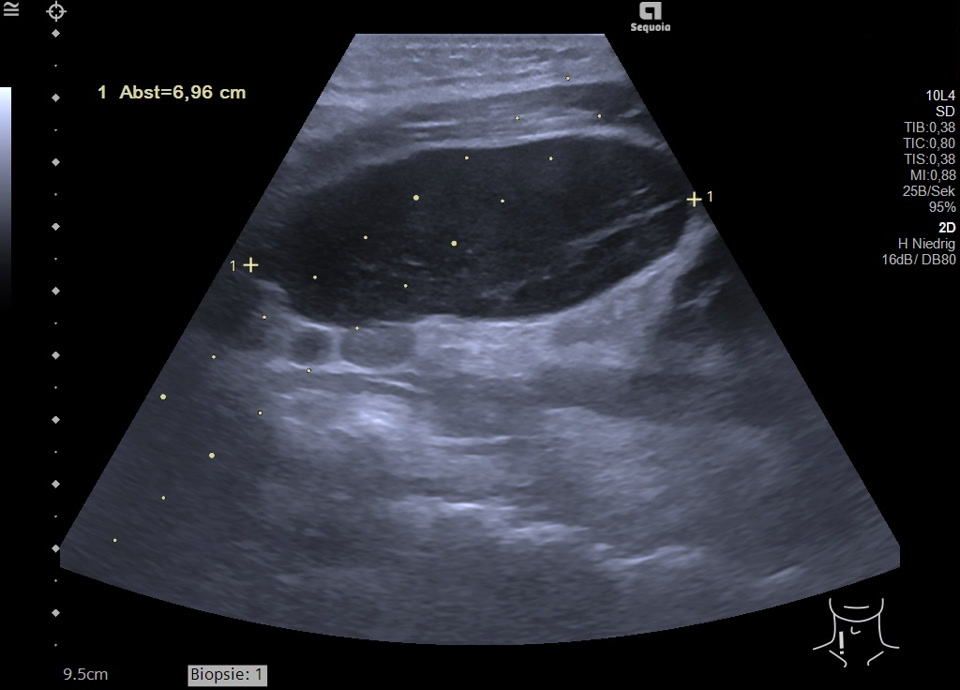

Malignitätsuspekte Raumforderung retroperitoneal und die A. mesenterica superior ummauernd (siehe Markierung), sonographische Punktion ergibt ein Non-Hodgkin Lymphom der B-Zell-Reihe (anaplastische Morphologie)

Malignitätsuspekte Raumforderung retroperitoneal und die A. mesenterica superior ummauernd, sonographische Punktion ergibt ein Non-Hodgkin Lymphom der B-Zell-Reihe (anaplastische Morphologie)